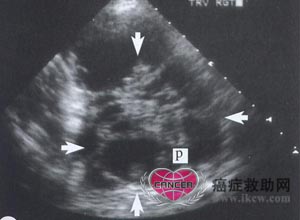

Ⅲ期卵巢癌。盆腔超声显示为复杂的多囊性肿块。可见囊性和实性成分,囊性成分中有不规则的壁和乳头状突起。